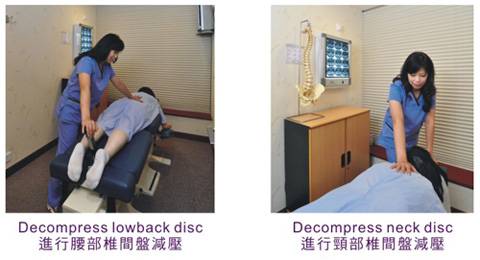

Cox® 椎間盤 減壓治療法-不倚靠止痛藥鎮痛,舒緩坐骨神經痛

至於脊科醫療方法,「Cox®椎間盤(軟骨)減壓治療法(Cox®Decompression Manipulation) 」,Cox®椎間盤 減壓治療法是由美國的Dr. James M. Cox於1960年發明。他使用了「槓桿」 和「減壓」 兩種不同的技術來操控脊椎的移動。

Cox®軟骨減壓治療特別有效地減輕腰背痛、脚痛及頸肩痛的症狀,對椎間盤突出、坐骨神經痛、脊椎狹窄症、脊椎滑脫症等脊科問題引發的痛症尤其顯著。

Cox®軟骨減壓治療是一個通過長期臨床研究和實證的治療法,亦是一個經過多方面引證能有效減除背痛的治療方法。不倚靠止痛藥及手術等入侵式治療方法,和其他治療比較,Cox®椎間盤 減壓是一個相對温和的治療法,並把疼痛盡量減至最低。